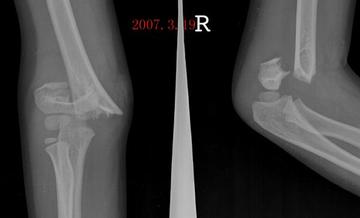

骨化性肌炎是肌肉逐渐变硬,发生骨化的一种疾病。多发生于20~30岁间的青年,男性多见。病因不清,可能与遗传和外伤有关。临床表现为局部肌肉变硬、变形,疾病发展到一定阶段会出现邻近关节僵硬和功能丧失。本病的治疗方法有保守、手术及康复治疗。在病程进展中,可导致肌质消损,关节强直,最终变成完全无力,只能做有限度的运动。因是良性病变,极少复发,但如手术切除不净,则可继续生长。